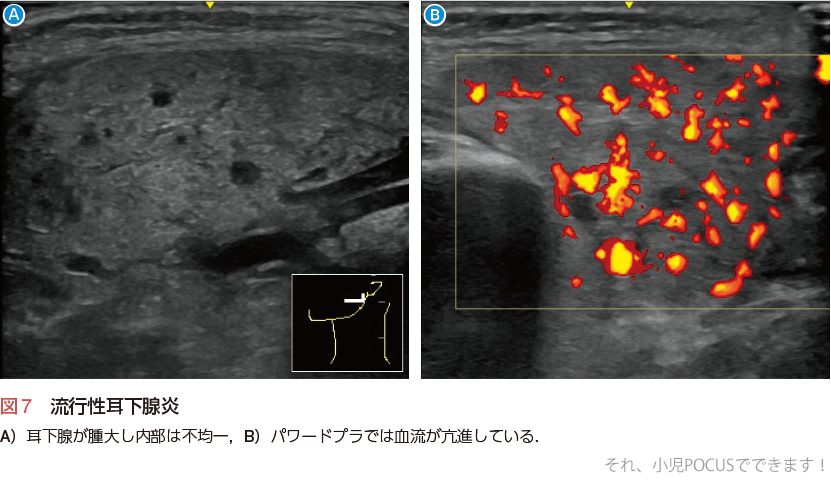

1)流行性耳下腺炎(おたふくかぜ)

ムンプスウイルスによる耳下腺炎で3〜6歳頃に多く,耳下腺は両側性ときに片側性に腫大します(図7A).エコーでは内部エコーは不均一でやや低エコーを呈します.腺管の拡張はみられません.カラードプラでは健側と比べて血流が亢進します(図7B).